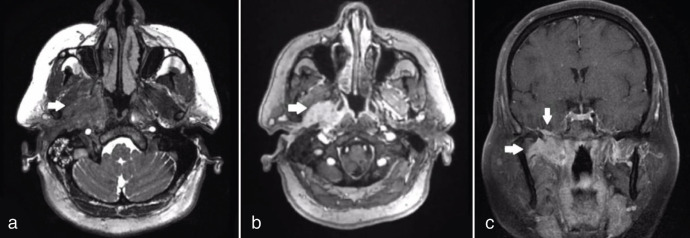

We report the case of a 56-year-old female recently diagnosed with well-differentiated squamous cell carcinoma of the external auditory canal. The patient underwent an 18F-fluorodeoxyglucose positron emission tomography/computed tomography for staging assessment. This examination revealed intense uptake in the right ear canals, tympanic cavity, eustachian canal, parapharyngeal area, and infratemporal fossa. Notably, we identified intracranial dural metastasis, which represents an uncommon site for metastatic spread in general.